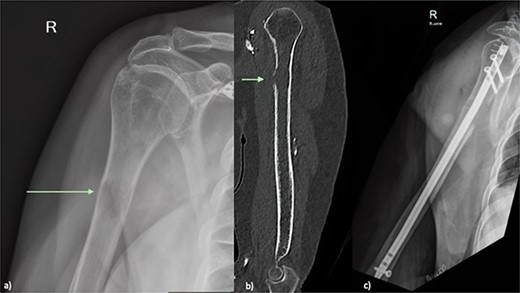

An X-ray of the right humerus demonstrated a lytic lesion in the proximal humeral diaphysis with metastatic features (Fig. 1a). Subsequent computed tomography (CT) of the right humerus demonstrated a medullary metastasis at high risk of pathological fracture (Fig. 1b). Further imaging with CT chest–abdomen–pelvis demonstrated a necrotic mass in the tail of the pancreas (Fig. 2) with direct extension into the left adrenal gland and suspected liver metastases.

(a) Plain radiograph of the right humerus demonstrating a lucent lesion in the proximal humerus with cortical destruction indicated by green arrow (b) Sagittal CT of the right humerus showing a proximal humeral lesion with breach of the anterior cortex (green arrow) at high risk of pathological fracture (c) plain radiograph Day 1 post prophylactic intramedullary nail of right humerus.

Due to the calculated fracture risk, a prophylactic intramedullary humeral nail was recommended and performed [1]. Tissue samples were obtained by focal reaming and curettage and sent for histopathology. A diagnosis of metastatic adenosquamous carcinoma with mucoepidermoid morphology of pancreatic origin was made.